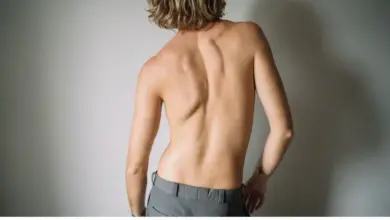

Escoliose na Coluna: Causas, Sintomas e Tratamentos

A escoliose na coluna é um desvio que faz a coluna se curvar para um dos lados, tirando parte do…